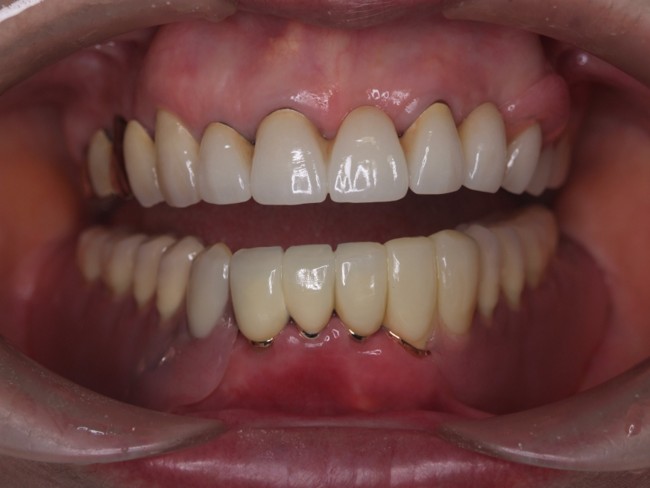

インプラント治療・セラミック治療・金属床コーヌス義歯(部分入れ歯)の症例紹介(三隅歯科クリニック)

三隅 賢祐(三隅歯科クリニック)

症例詳細

| 主訴 | 50代女性 他院でいれた入れ歯の具合が良くない。歯を白くしたい。歯並びも気になる。しっかり噛めるようになりたい |

| 治療内容 | インプラント治療、セラミック治療、金属床コーヌス義歯(部分入れ歯)を行いました。 |

| 治療費 | 2,400,000円(税込み) |

| 治療期間 | 8か月 |

| 治療回数 | 30回 |

| 想定されたリスク | 重度の歯周病で臼歯部の歯槽骨がかなり吸収していたため、インプラントが脱落するリスクがありました。 |